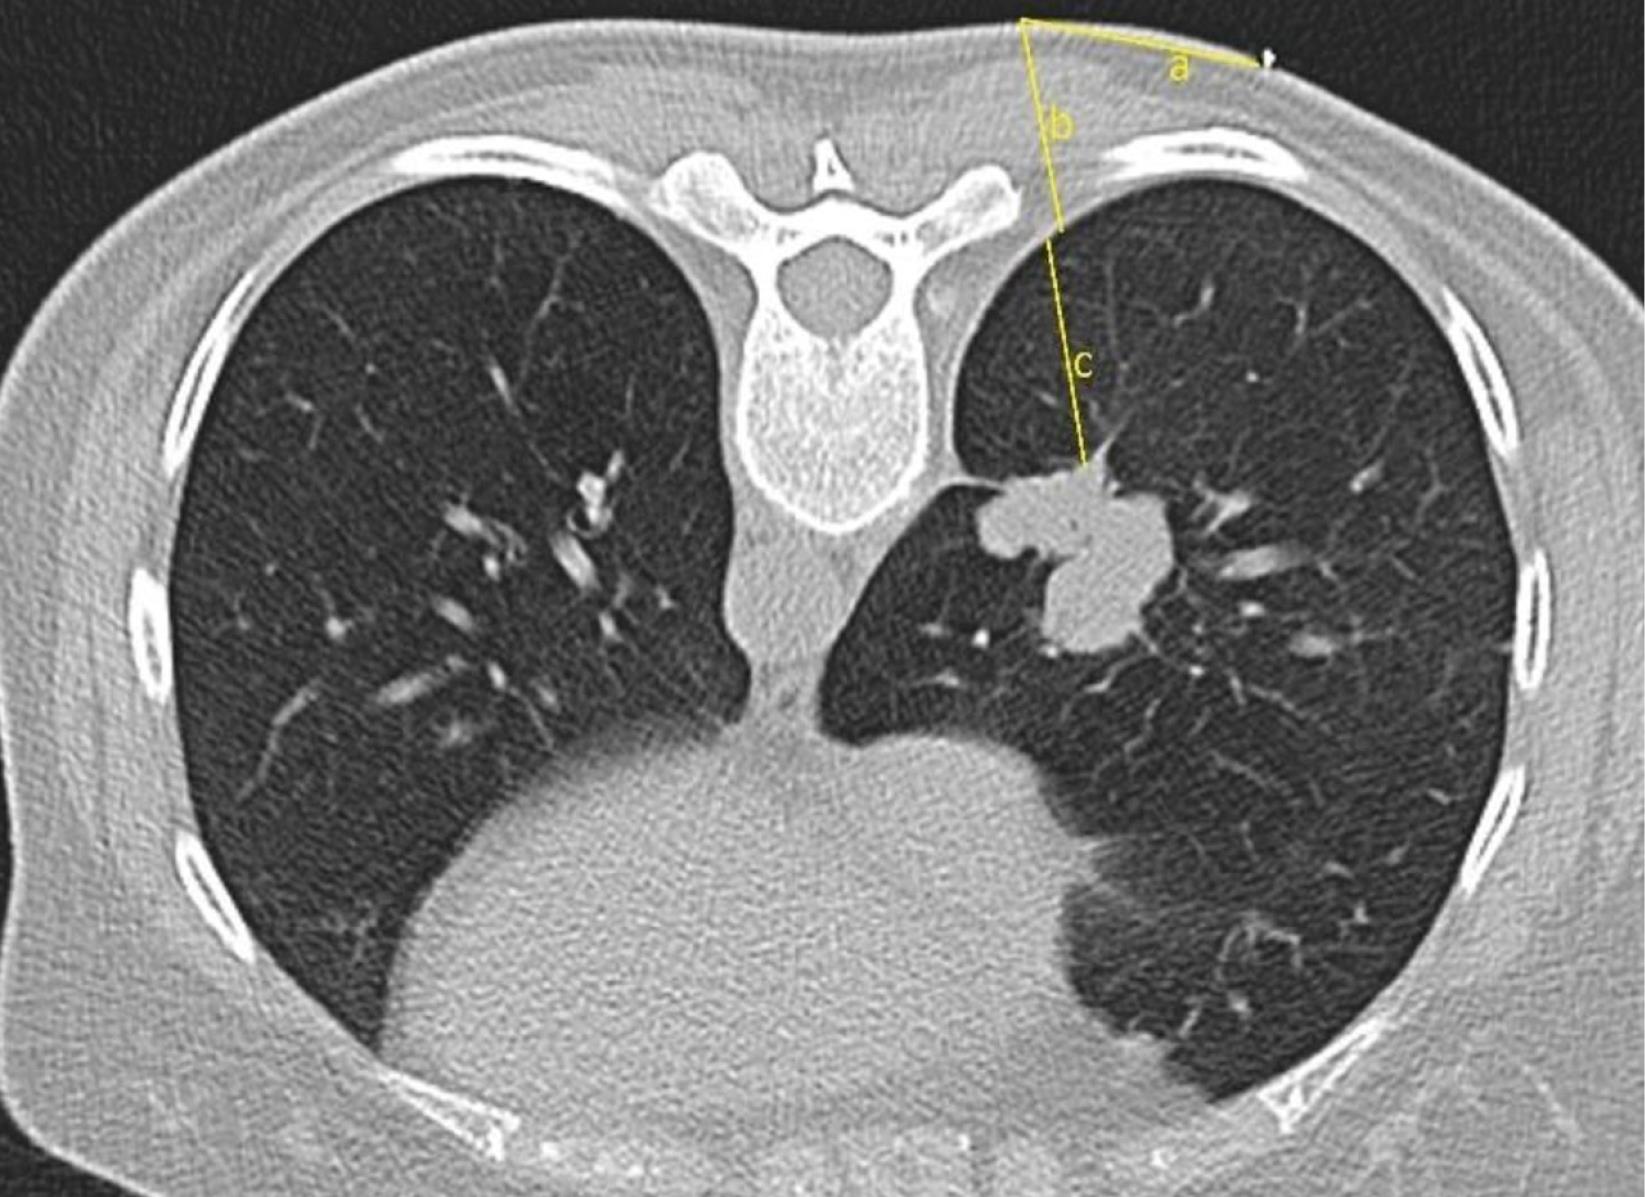

The location and distance of entry to the lesion have been rescheduled according to this image. The skin-pleura and pleura-lesion distances were calculated (Figure 2). Care was taken to ensure that there are no areas such as fissures, bullae, major vascular structures, ribs, and scapula that prevent entry in the entry tracing. The process was continued either by changing the gantry angle or finding another safe way. After the entry point, angle and trace were determined and the area was cleaned with an antiseptic solution and covered with a perforated sterile drape. Local anesthesia was administered to the entry point under sterile conditions. 5-10 cc prilocaine HCL (Citanest®) was used for local anesthesia.

Figure 2.

Measurement of the distances from the skin to the most appropriate angle (a), from the possible entry point to the pleura (b), and from the pleura to the mass (c)